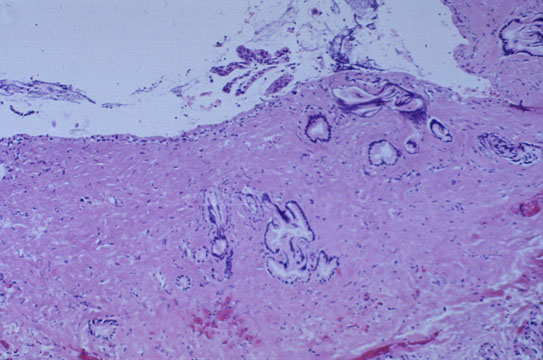

Fig 12 - HYLAR BILE DUCTS

Are one for the right lobe and one for the left.&nbs; There are,however recesses and outpouchings connected with them which are involved in the resorption and concentration of bile.  Cholelithiasis may occur in these ducts.

About 10-12 mm in diameter,they is lined by mucosa with short folds supported by fibrous tissue with elastic fibers.They have glandular recesses in the muscular wall which should not be iterpreted as infiltrating malinancy. These gland are surrounded by elastic fibers,therefore an elastica stain should solve the problem.